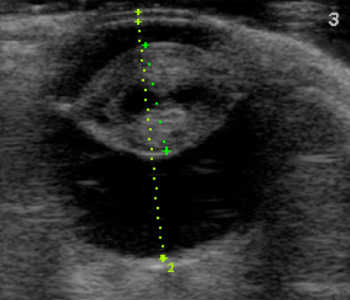

【超音波(エコー)検査】

目の中、特に硝子体や網膜など水晶体の裏側がどのような状態なのか調べます。エコー検査により、白内障の混濁状態や網膜剥離や眼内出血などの合併症の評価を行います。

犬 白内障

白内障(成熟)